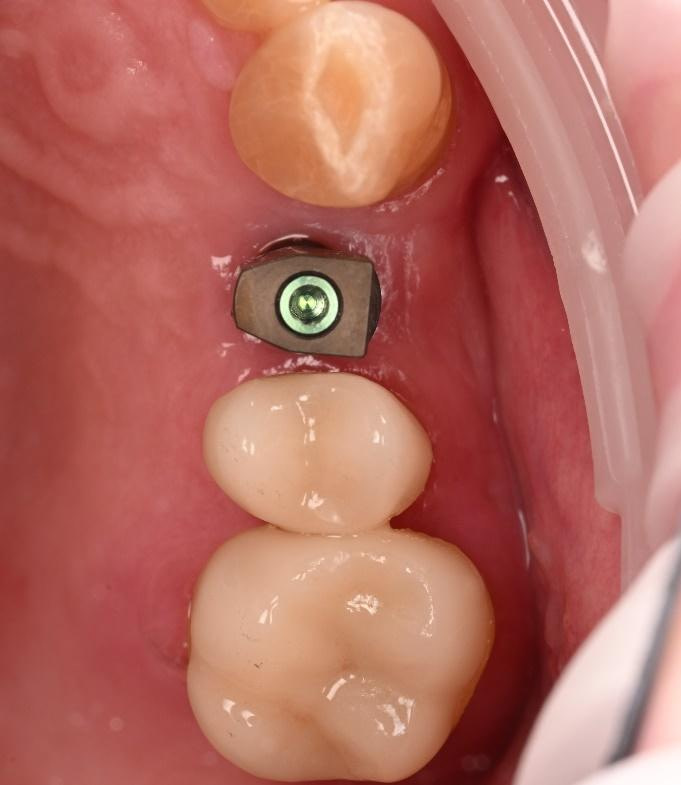

Implant detection matches the scan body in the intraoral scan with the digital library. A colour scale is given to show the accuracy of the matching (Green is good).